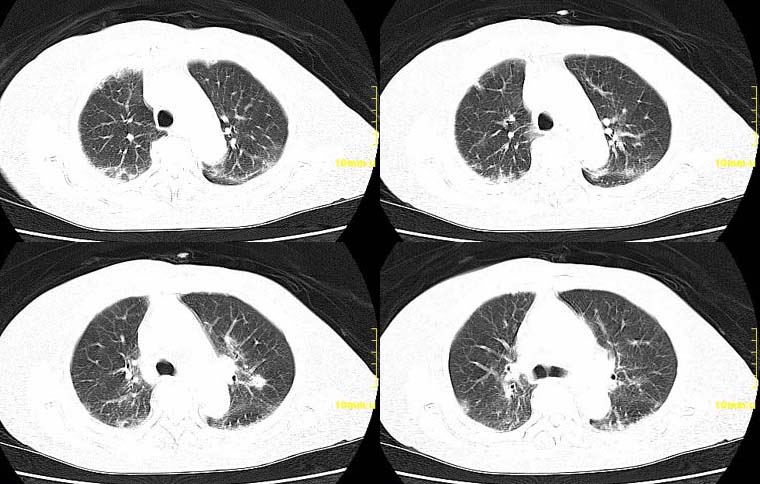

请大家讨论右下肺占位性质。ct值约35-55hu

右肺中央型肺ca伴纵隔淋巴及肺内播散转移。

右下中央型肺癌伴右肺门、纵隔淋巴结转移,双肺肺转移